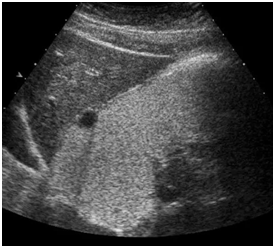

七、病例展示

胃间质瘤

胃溃疡

急性胃炎

胃癌